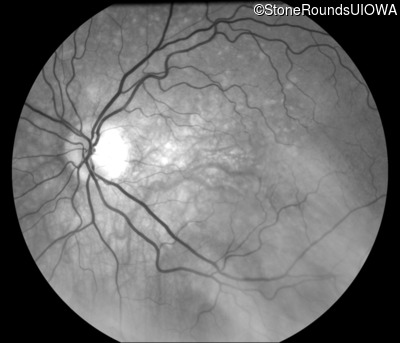

Fundus Photography - Right - 20/15 -2 sc

Exemplar